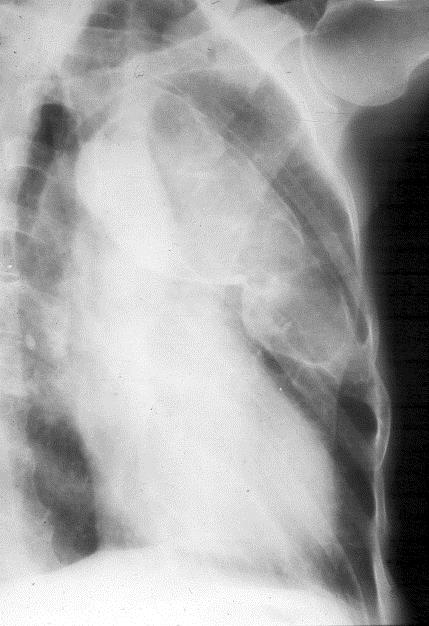

The lesions are often long and expand the bone (Figure 8).

Figure 8: FD – Oblique view of the left 4th rib with expansion.